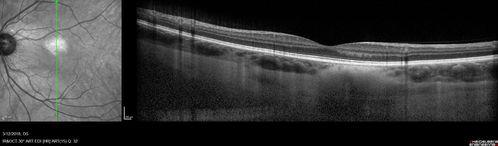

Choroidal Nevus - Macula - Flat

37 year old female with 5 year stable nevus Left eye - OCT shows flat nevus (EDI scan)